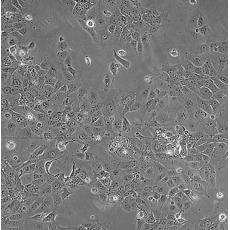

中文名稱 人非小細胞肺癌細胞

組織來源 肺腺癌;女性

生長特性 adherent

形態(tài)特征 epithelial

細胞描述 This lung adenocarcinoma has an acquired mutation in the EGFR tyrosine kinase domain(E746-A750 deletion).